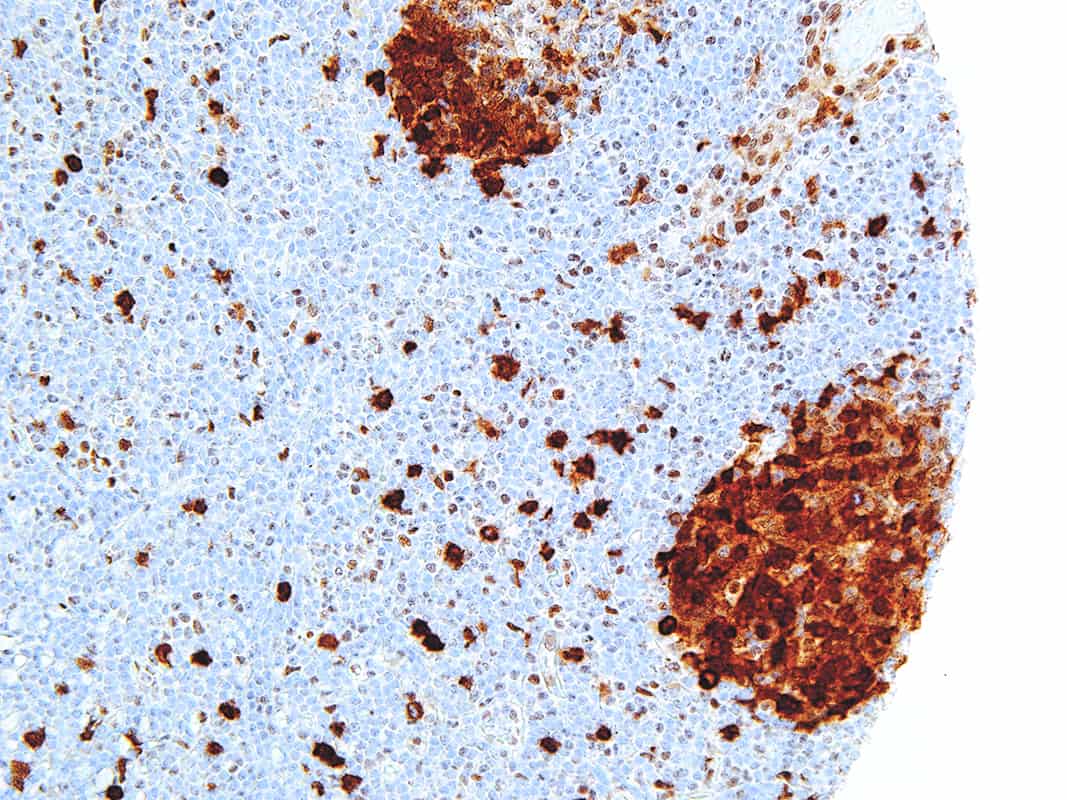

Thymidylate Synthase

Thymidylate Synthase (TS) is a crucial enzyme responsible for the synthesis of 2′-deoxythymidine-5′-monophosphate (dTMP) a precursor for thymidylate which is necessary for DNA replication and repair from 2′-deoxyuridine-5′-monophosphate (dUMP). In terms of cancer, TS is an important target for cancer treatment as the inhibition of TS and therefore nucleotide synthesis necessary for cell growth has shown to be a vital part for successful treatment against colorectal, pancreatic and breast cancers.

| Clone | IHC697 |

| Source | Mouse Monoclonal |

| Positive Control | Colon Cancer |

| Dilution Range | 1:100 – 1:400 |